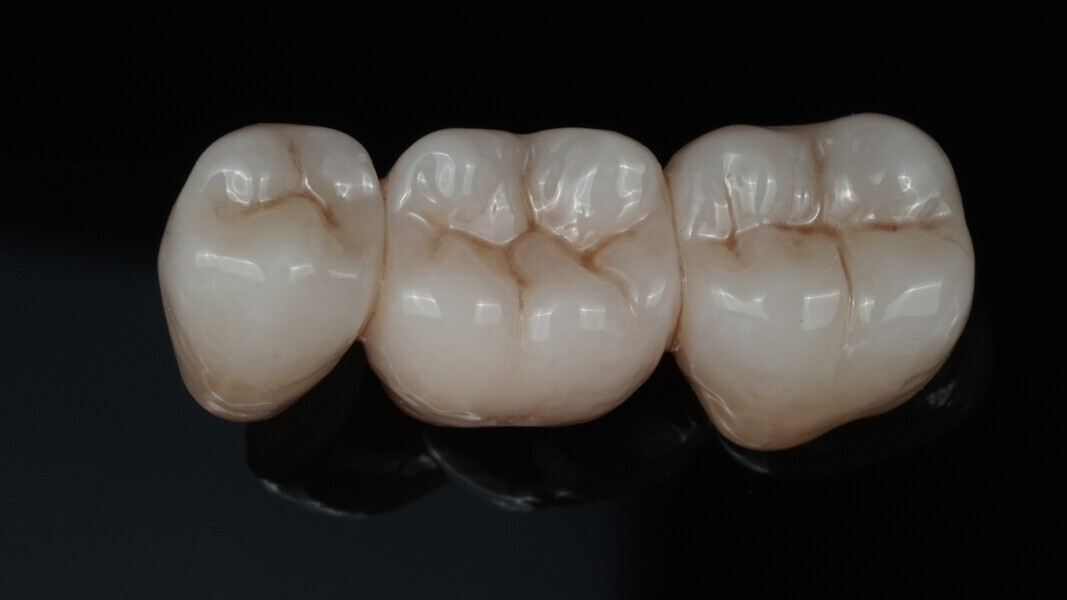

Fig. 10: Appearance of the bridge after two glaze firings.